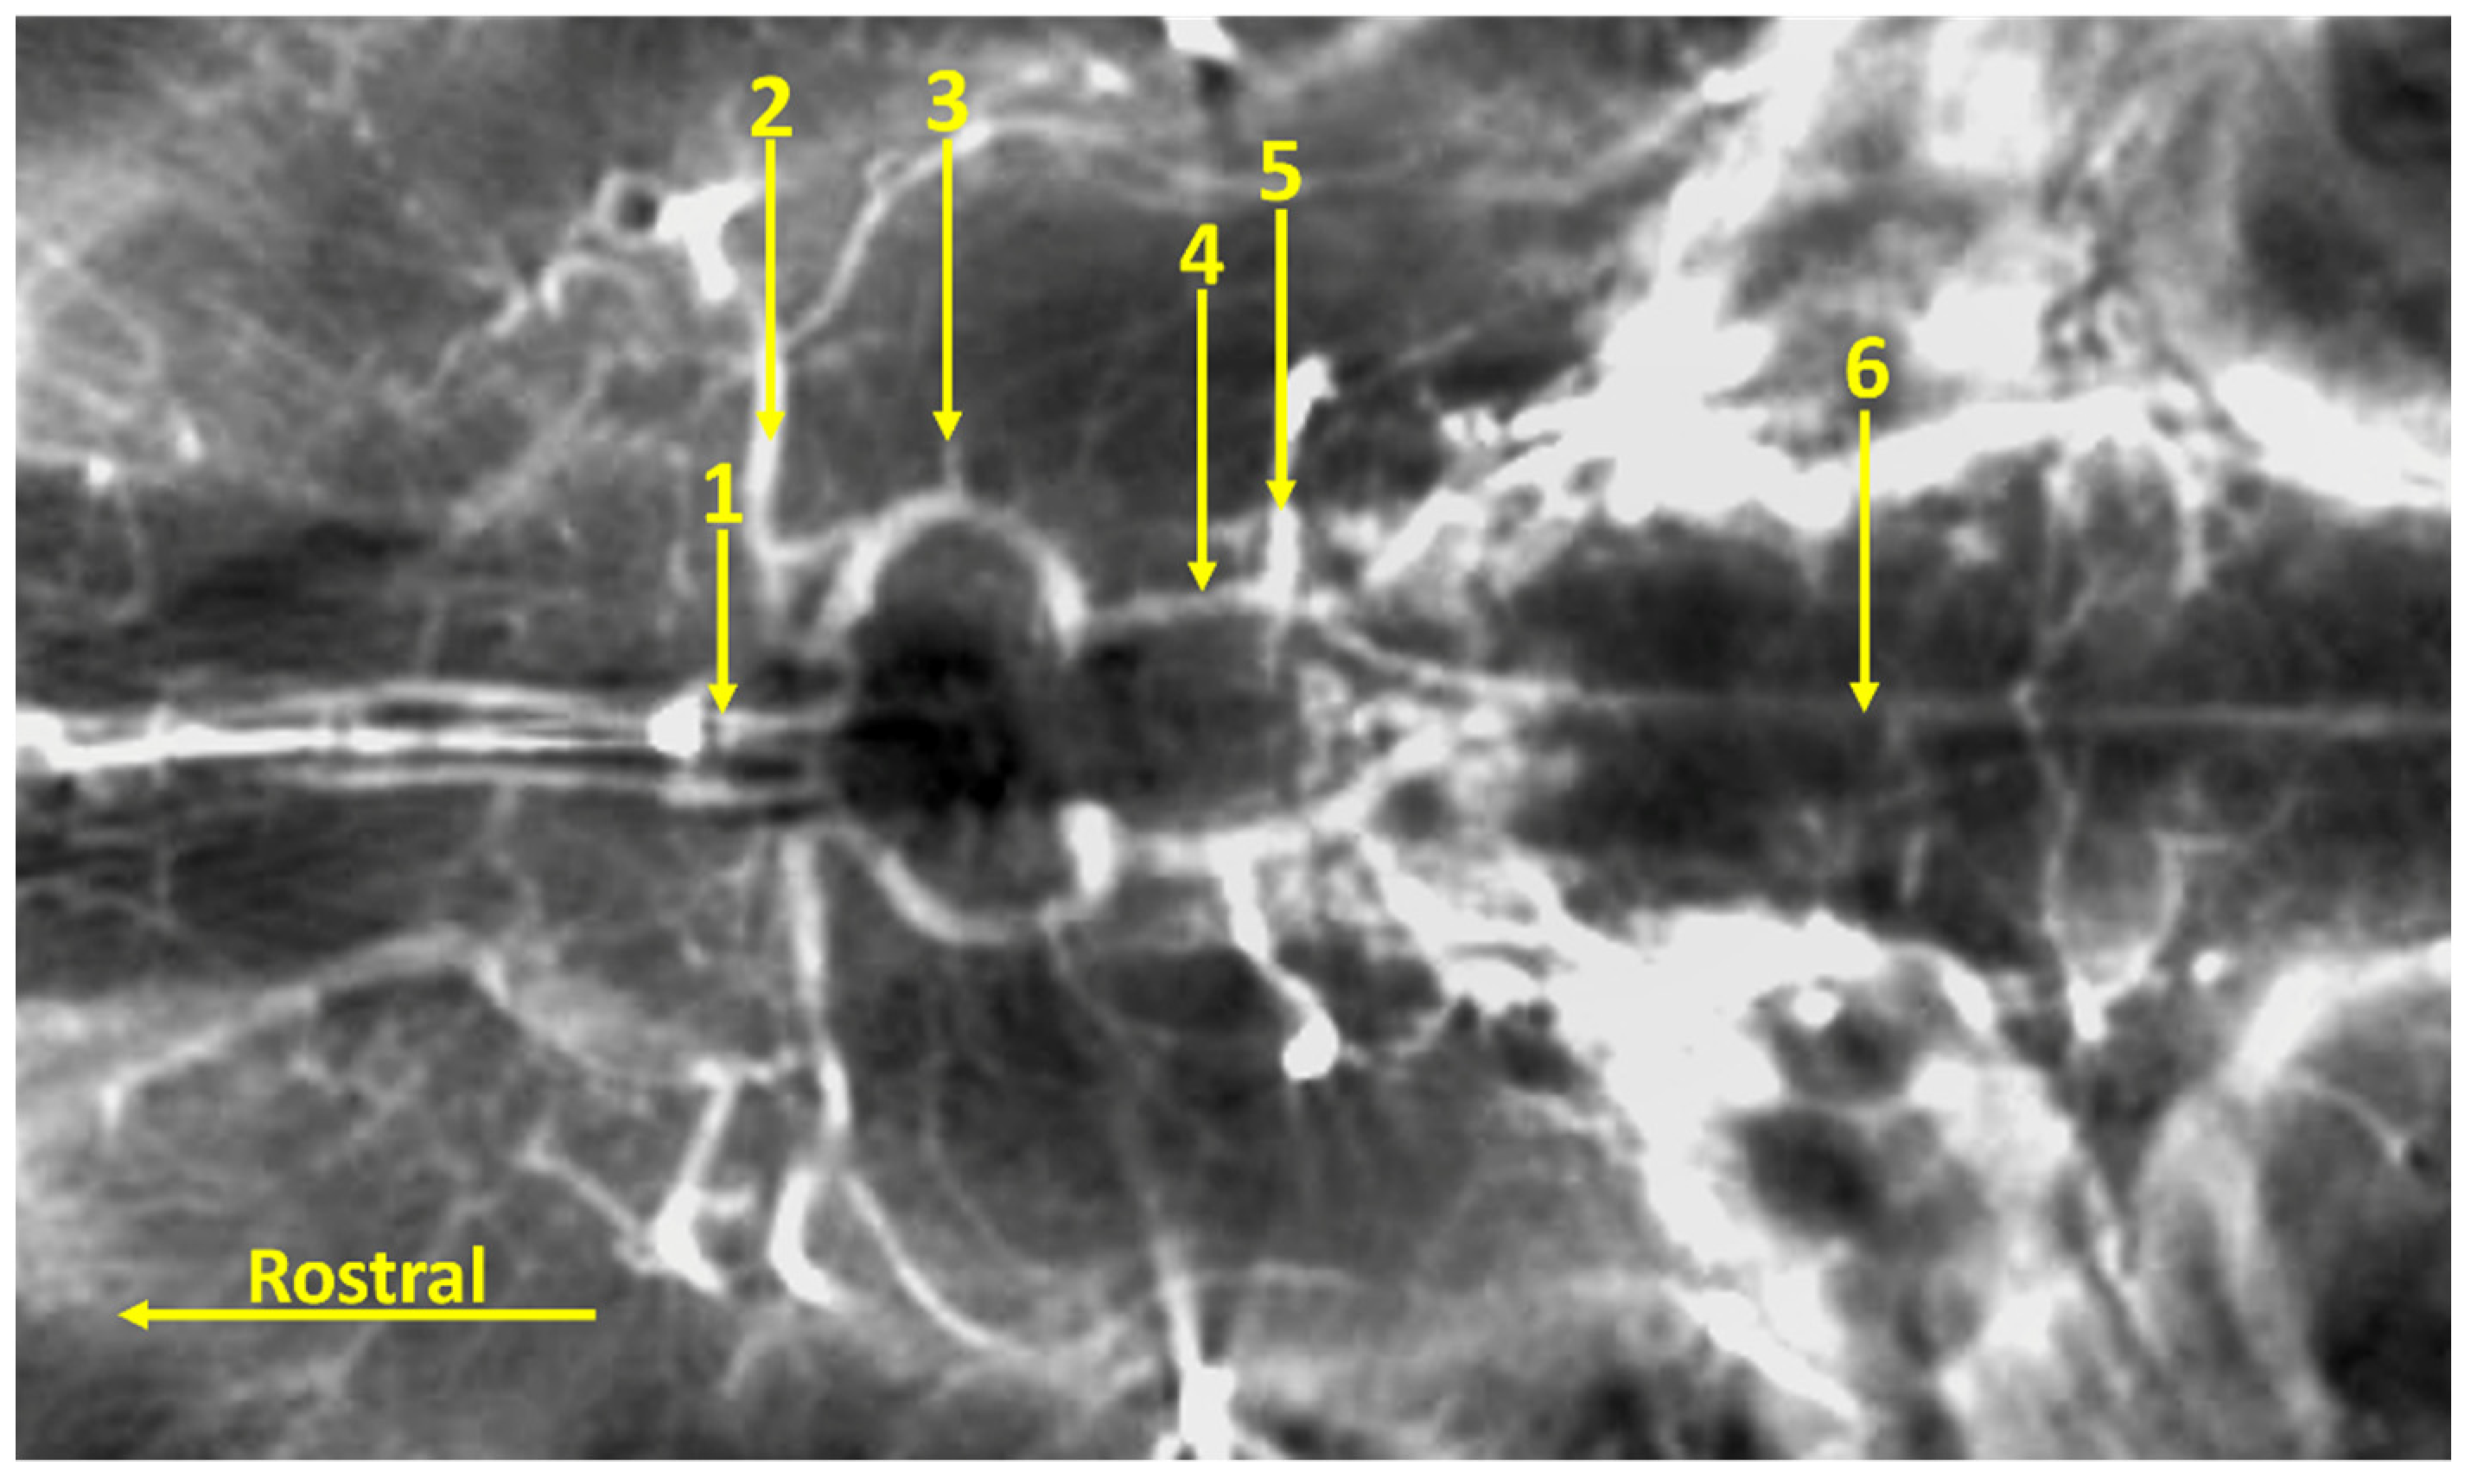

The Arterial Circle of the Brain in the Bawean Deer (Axis kuhlii)

3. Results